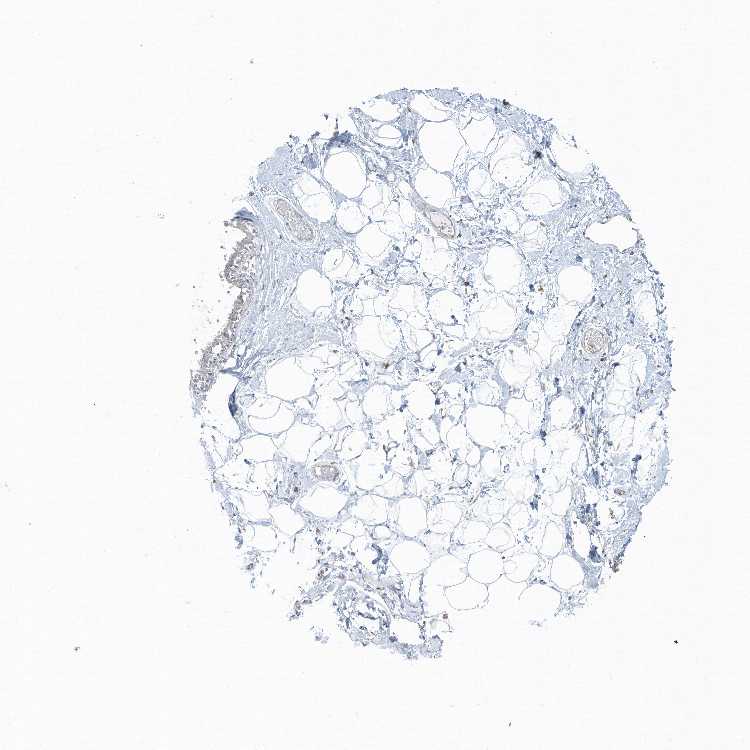

BREAST - Antibody stainingi

Antibody staining in the annotated cell types in the current human tissue is reported as not detected, low, medium, or high, based on conventional immunohistochemistry profiling in selected tissues. This score is based on the combination of the staining intensity and fraction of stained cells.

Each image is clickable and will lead to virtual microscopy that enables deeper exploration of all samples and also displays staining intensity scores, fraction scores and subcellular localization as well as patient and tissue information for each sample.

Antibody HPA041264Antibody HPA041271Antibody CAB037330

Adipocytes HighNot detectedNot detected

Glandular cells HighLowNot detected

Myoepithelial cells HighHighNot detected